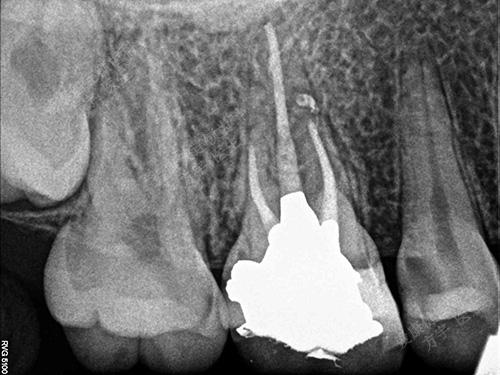

术中